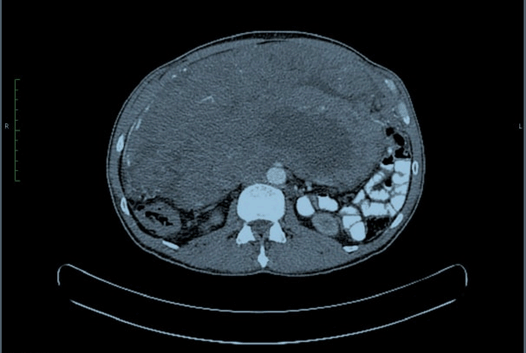

PET-CT scan showed a 26.3x24.3x11.3 cm, abdominopelvic mass extending into abdominopelvic cavity with splaying of large and small bowel and indenting right kidney and IVC, Displacing right lobe of liver (Figure 1) and (Figure 2).

Figure 1: Axial view of contrast enhanced computed tomography scan.